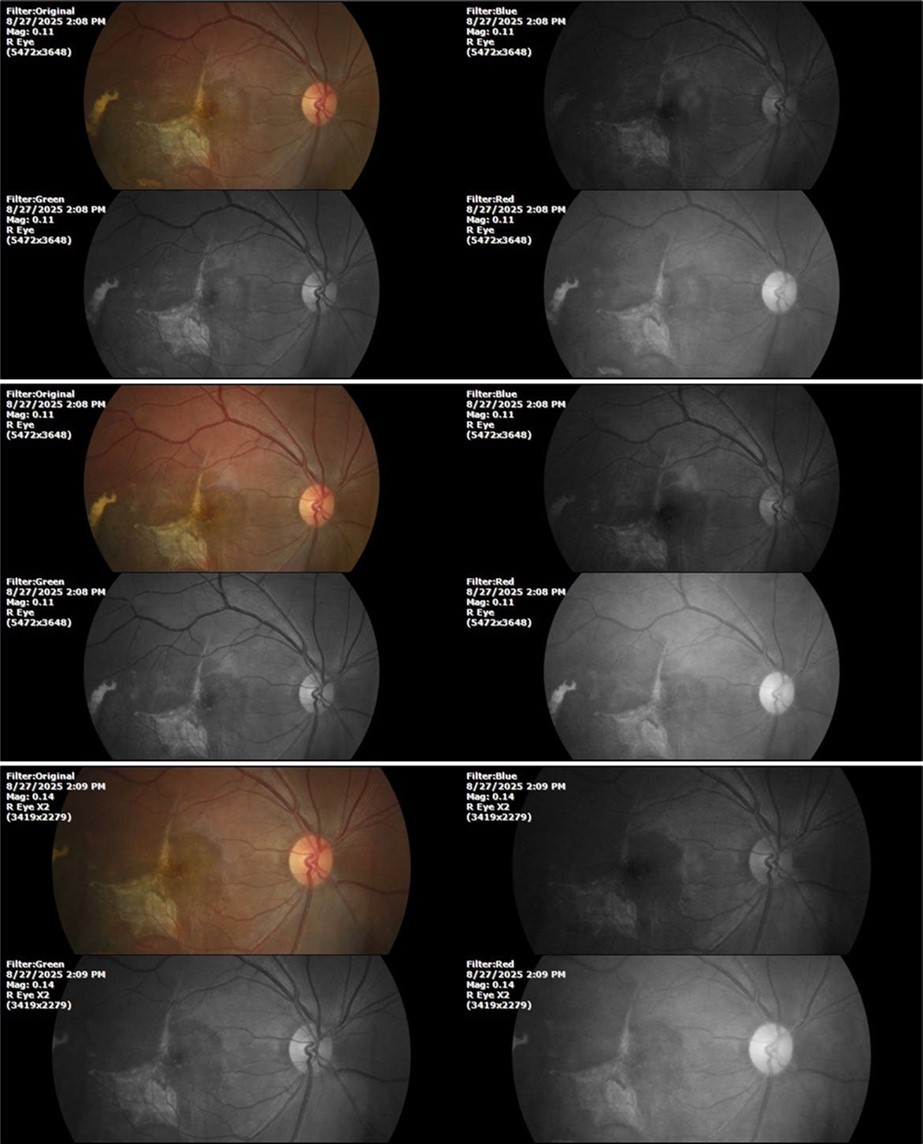

August 26, 2025

It's been fine, there's only a little veil that prevents it from seeing well completely, although it's very transparent (Figure 31, Figure 32, Figure 33, Figure 34, Figure 35, Figure 36).

++/++

Figure 31.The photograph of the right eye shows an almost normal mirror reflection, as well as a better pupillary dilation.

Figure 32.The macro photograph of the right eye shows us a cornea, anterior camera, and crystalline lens in very good condition.

Figure 33.The 3 previous photographs show that whitish mass has almost completely disappeared, and to date only a remnant remains on the left side of the photograph. The chorioretinal scar that is now observed corresponds to the area affected by the blunt trauma, which presumably caused rupture of Bruch's membrane. Fortunately, the macular region has recovered almost in its entirety, so the impairment in central vision was minimal.

Figure 8.The photograph of the superior temporal region of the retina of the right eye shows the extent of subretinal bleeding as well as retinal edema.

Figure 9.The extent of bleeding, mainly subretinal, is extensive and of significant volume, suggesting choroid rupture in this area.

Figure 10.The location of the bleeding is mainly subretinal, although blood is seen in minimal quantity in the vitreous body.

Figure 27.The three previous photographs of the right fundus show that the whitish mass composed mainly of phantom cells continues to decrease.